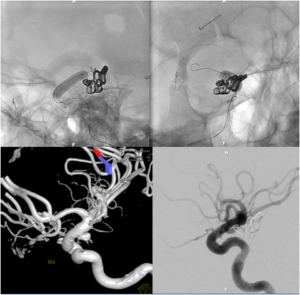

Pipeline Embolization Device Placement for Treatment of Unruptured Aneurysms

Flow diversion is an endovascular technique, used primarily for the treatment of unruptured intracranial aneurysms, whereby a tubular piece of mesh with very small interstices or “flow diverter” is placed inside the parent blood vessel to divert blood flow away from the aneurysm itself.

During a flow-diversion procedure procedure, a microcatheter is navigated beyond the aneurysm without having to enter the aneurysm sac itself. The flow-diverting device is then carefully deployed across the neck of the aneurysm in the parent blood vessel. The only currently approved FDA flow diverting device is the Pipeline™ Embolization Device (PED).